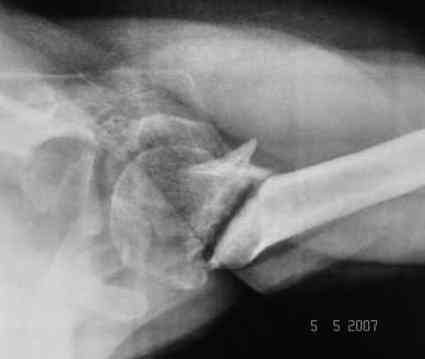

Looking at his previous x-rays, I was thinking of refixing the greater tuberosity, however got anaxillary view done today which was never done during this period and this shows non-union.

It looks like the initial injury was a head splitting fracture. Presently the patient has a non-union at the level of the anatomical neck with displaced tuberosities. I would tackle the non-union, and would try to replace the tuberosities, a difficult procedure. I would use the proximal humerus locking plate from the AO.